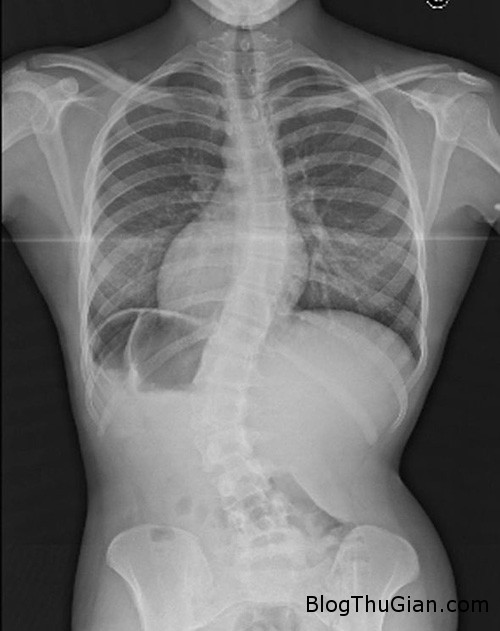

Leanne Roberts, 18 tuổi, trở nên chán nản khi bị chẩn đoán mắc chứng vẹo cột sống nặng cách đây hai năm. Căn bệnh lạ khiến cột sống của cô cong như hình chữ S.

Cột sống của Leanne bị cong thành hình chữ S. Ảnh: Caters